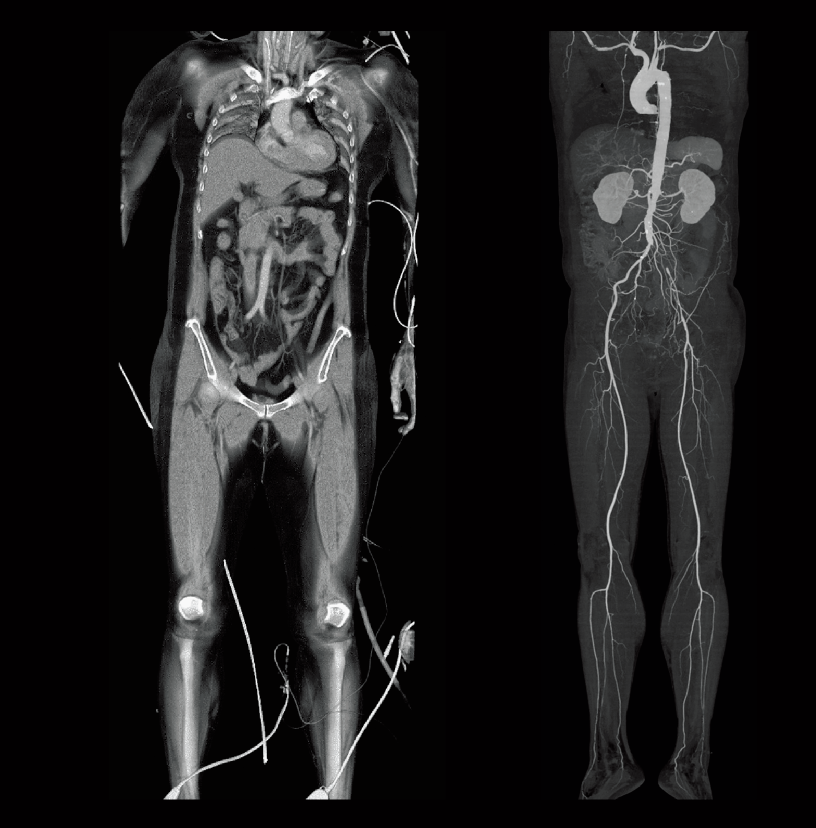

Oclusión aórtica abdominal

Desaturación intraoperatoria de oxígeno (izquierda)

Oclusión de la arteria ilíaca común izquierda (derecha)